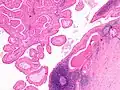

The appearance of this tumor under the microscope is unique. There are cystic spaces surrounded by two uniform rows of oncocytes, which are epithelial cells with abundant, granular, eosinophilic cytoplasm.[7] The cystic spaces have epithelium referred to as papillary infoldings that protrude into them. Additionally, the epithelium has lymphoid stroma with germinal center formation.

Low magnification micrograph of a Warthin tumor arising from the parotid gland. -

Histopathology of Warthin tumor in the parotid gland. H&E stain. -